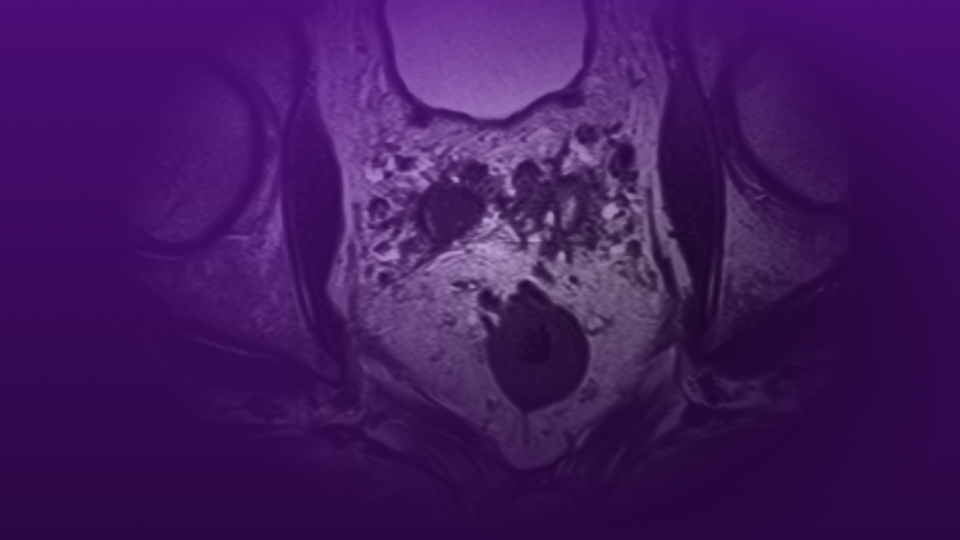

Across nearly every metric of hospital and outpatient quality, NYU Langone Health ranks at the top. As well as having the most top ranked specialties in New York (tied) according to U.S. News & World Report, 13 specialties are ranked nationally – with nine ranked in the top 5 – and NYU Langone is on the honor roll of the top hospitals in the nation. Our digital journal, Physician Focus, highlights our latest innovations and research highlights.